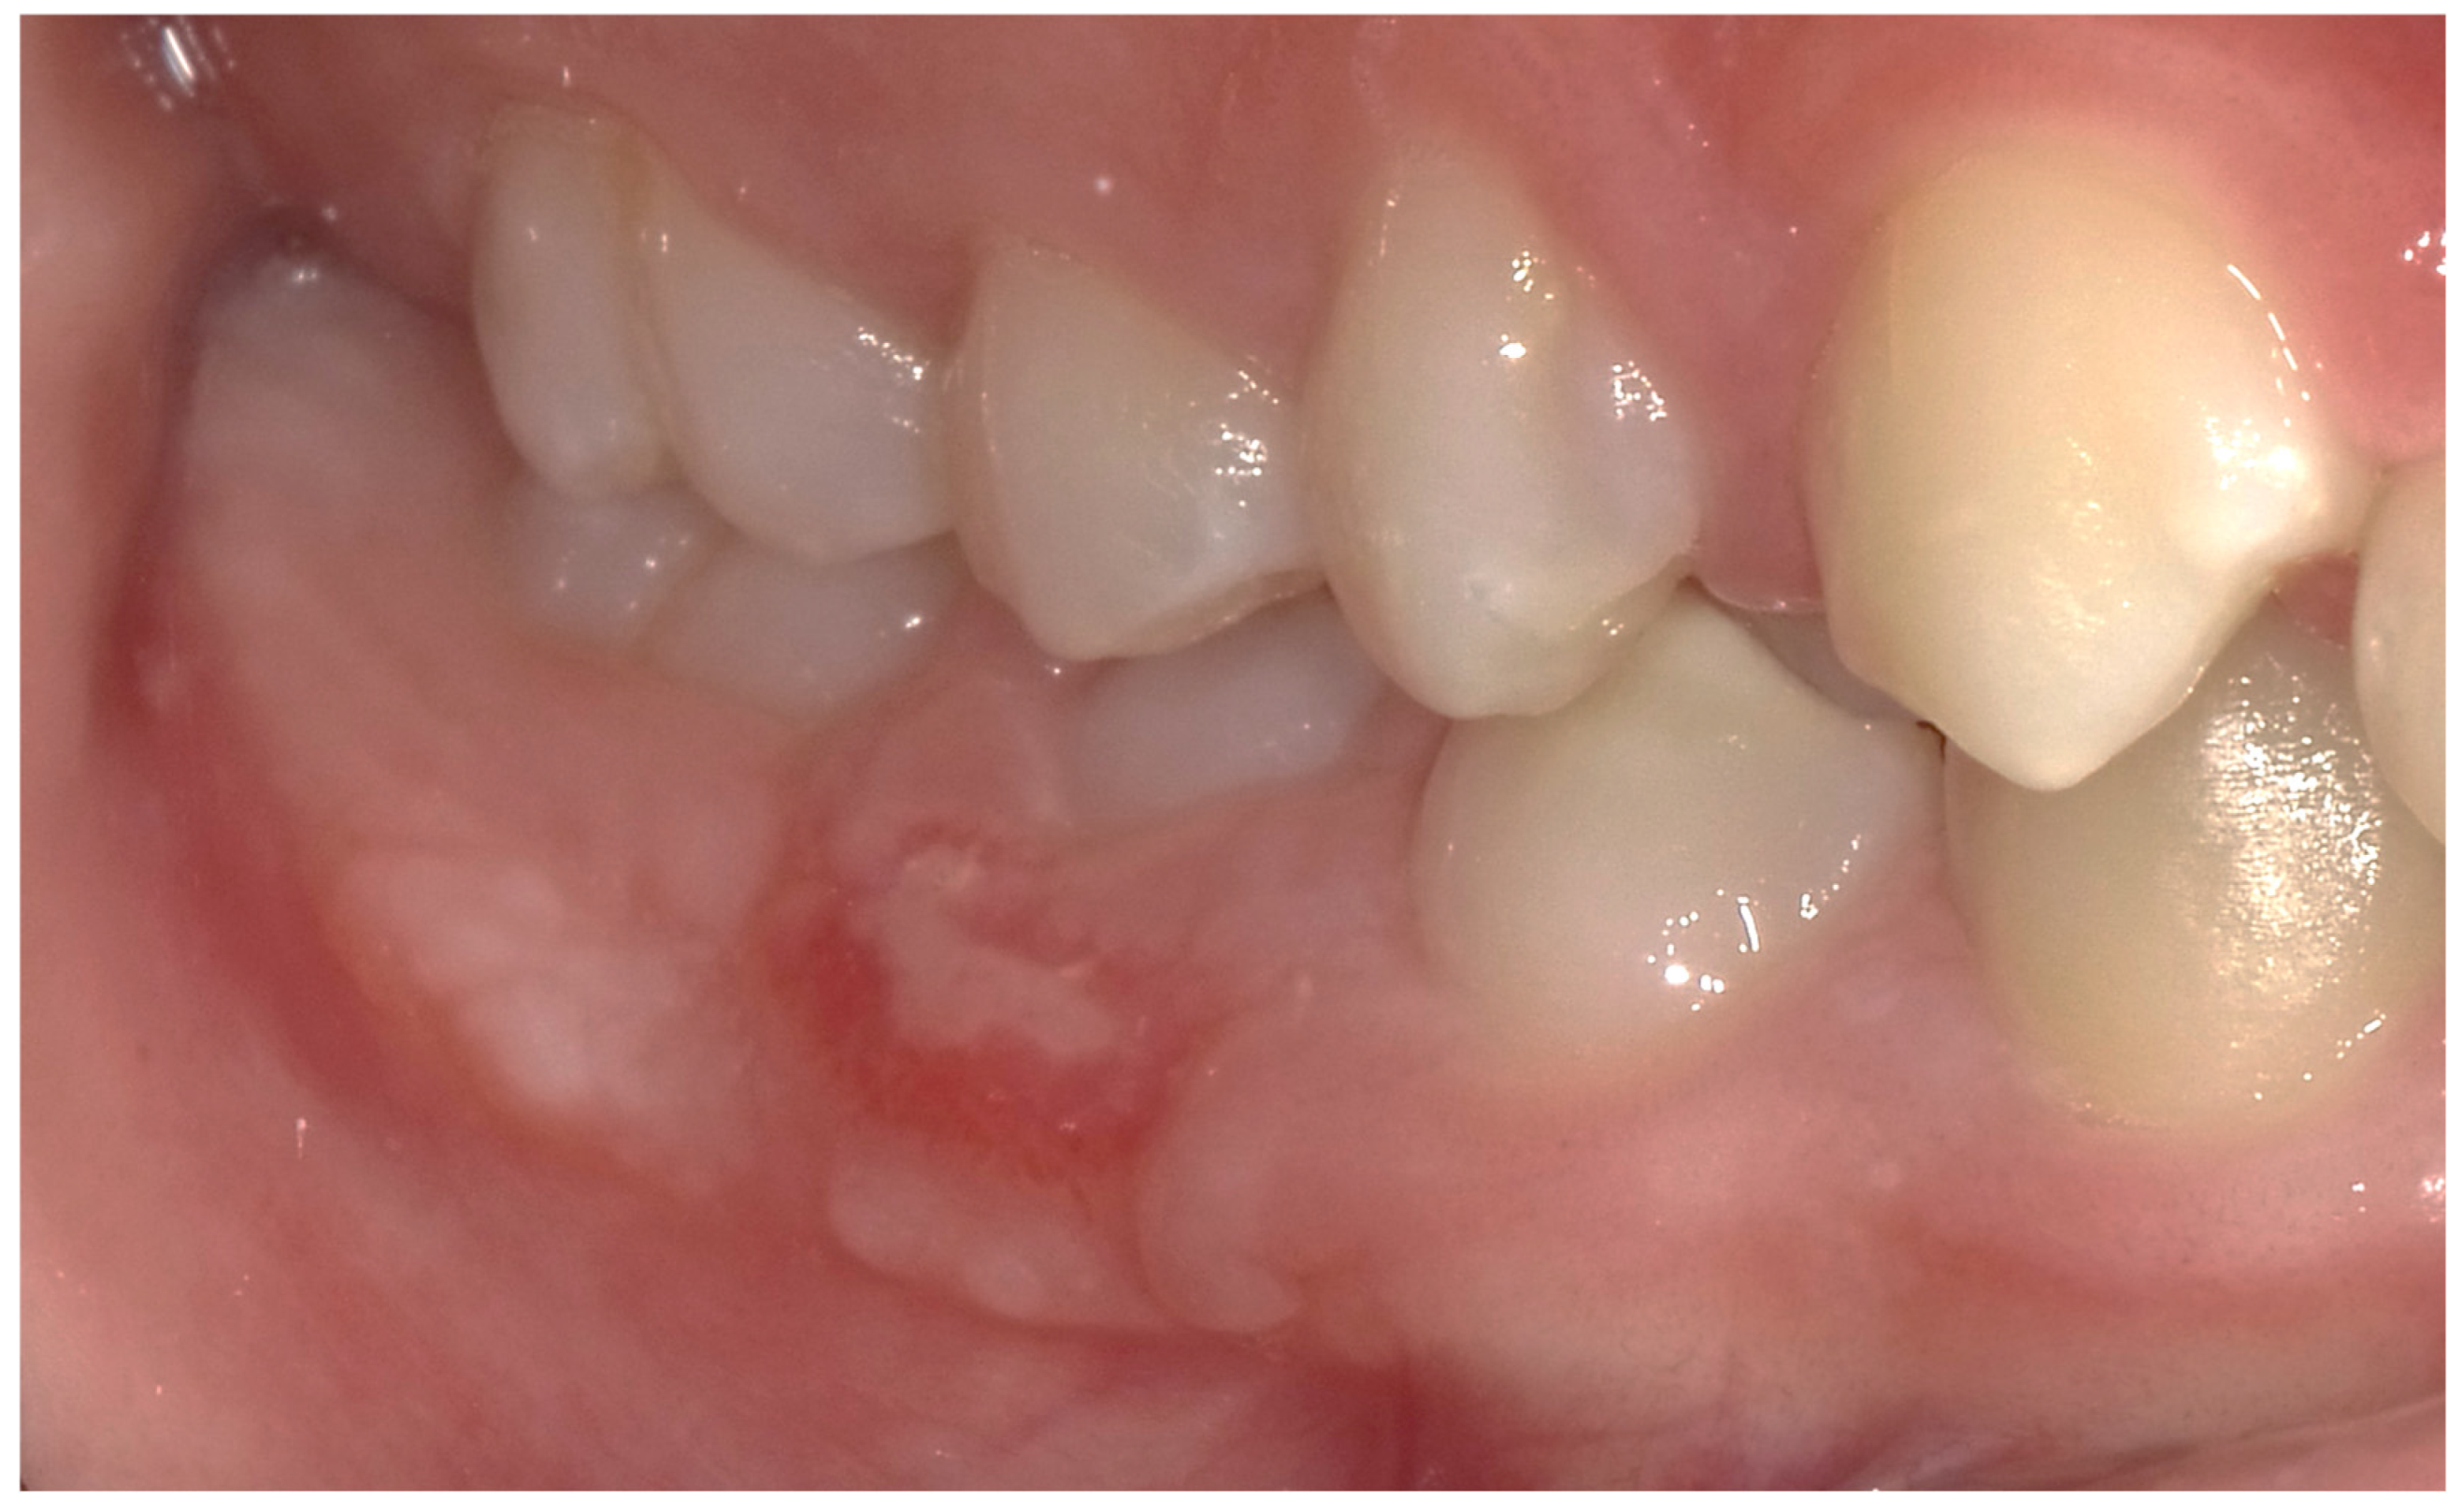

2.5. Follow-Up and Outcomes

3. Results